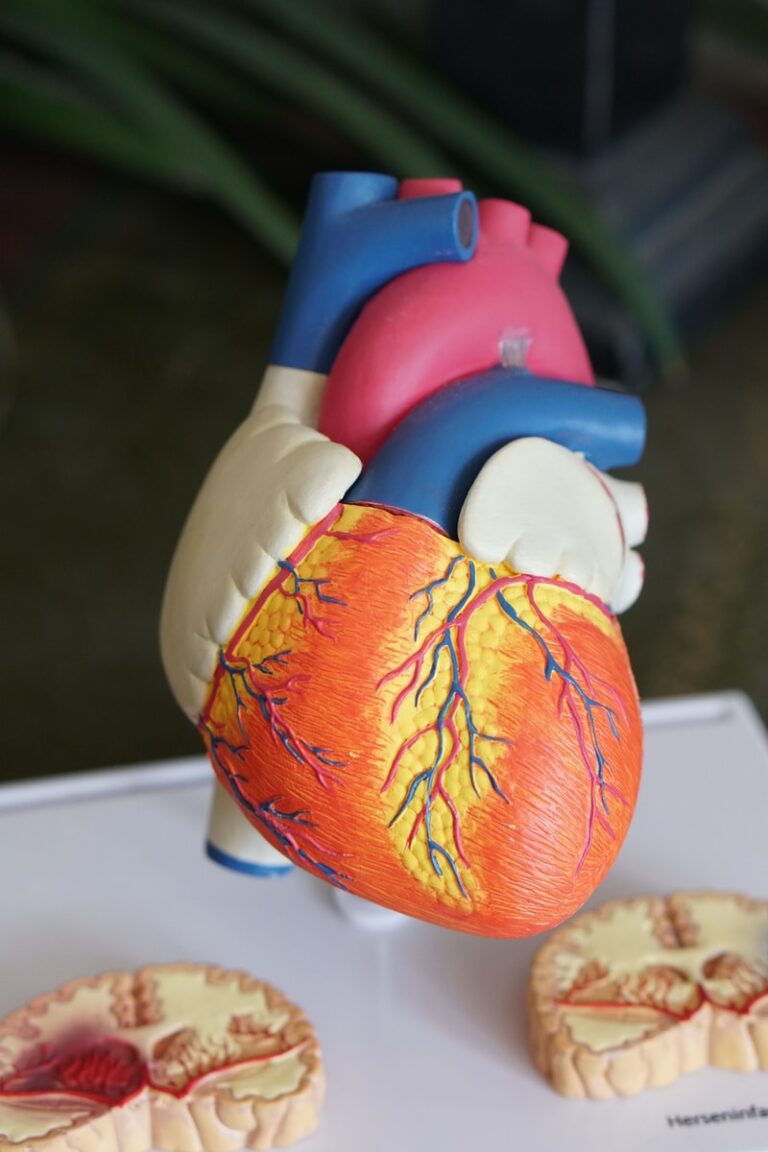

Look at a heart attack as an opportunity to refocus on healthy habits and control your risk factors for future cardiovascular disease.